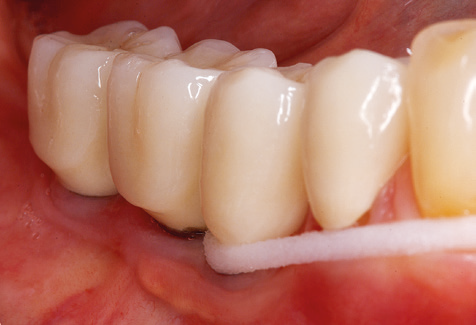

Standardised and regular risk-adapted care in the scope of SPT is the key to treatment success for the clinical long-term success in periodontically compromised patients. This is particularly true for patients fitted with implants following successfully completed periodontal treatment (Fig. 11a and b).

Before initiating the prosthetic treatment, it is advisable to inform the patient of the time and financial costs associated with the SPT (two to four SPT sessions per year for the rest of his/her life). This contributes significantly to ensuring the patient’s compliance. In addition, the practice is required to provide the rooms and staff necessary for the care of the periodontically treated patients.